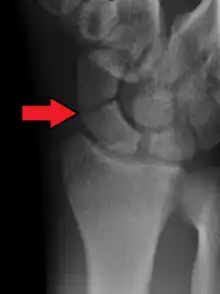

Le diagnostic de fracture est difficile à réaliser car les lésions éventuelles peuvent ne pas être immédiatement visibles sur les radiographies standard du poignet de face et de profil. On pratique aussi une radiographie avec incidences spéciales (inclinaison de 30° vers le coude) qui permettent de dérouler l'os et ainsi de visualiser plus précisément le trait de fracture[5].

Dans 1/4 des cas, l'examen clinique fait penser à une fracture, mais la radio ne le montre pas, alors qu'il y a réellement une fracture[6].

L'utilisation d'autres techniques d'imagerie médicale (scanner, IRM[7], scintigraphie osseuse, ce dernier examen semblant le meilleur du point de vue de la sensibilité et de la spécificité[8]) permet d'être plus sur du diagnostic, même si la scintigraphie conduit parfois au surdiagnostic[9].